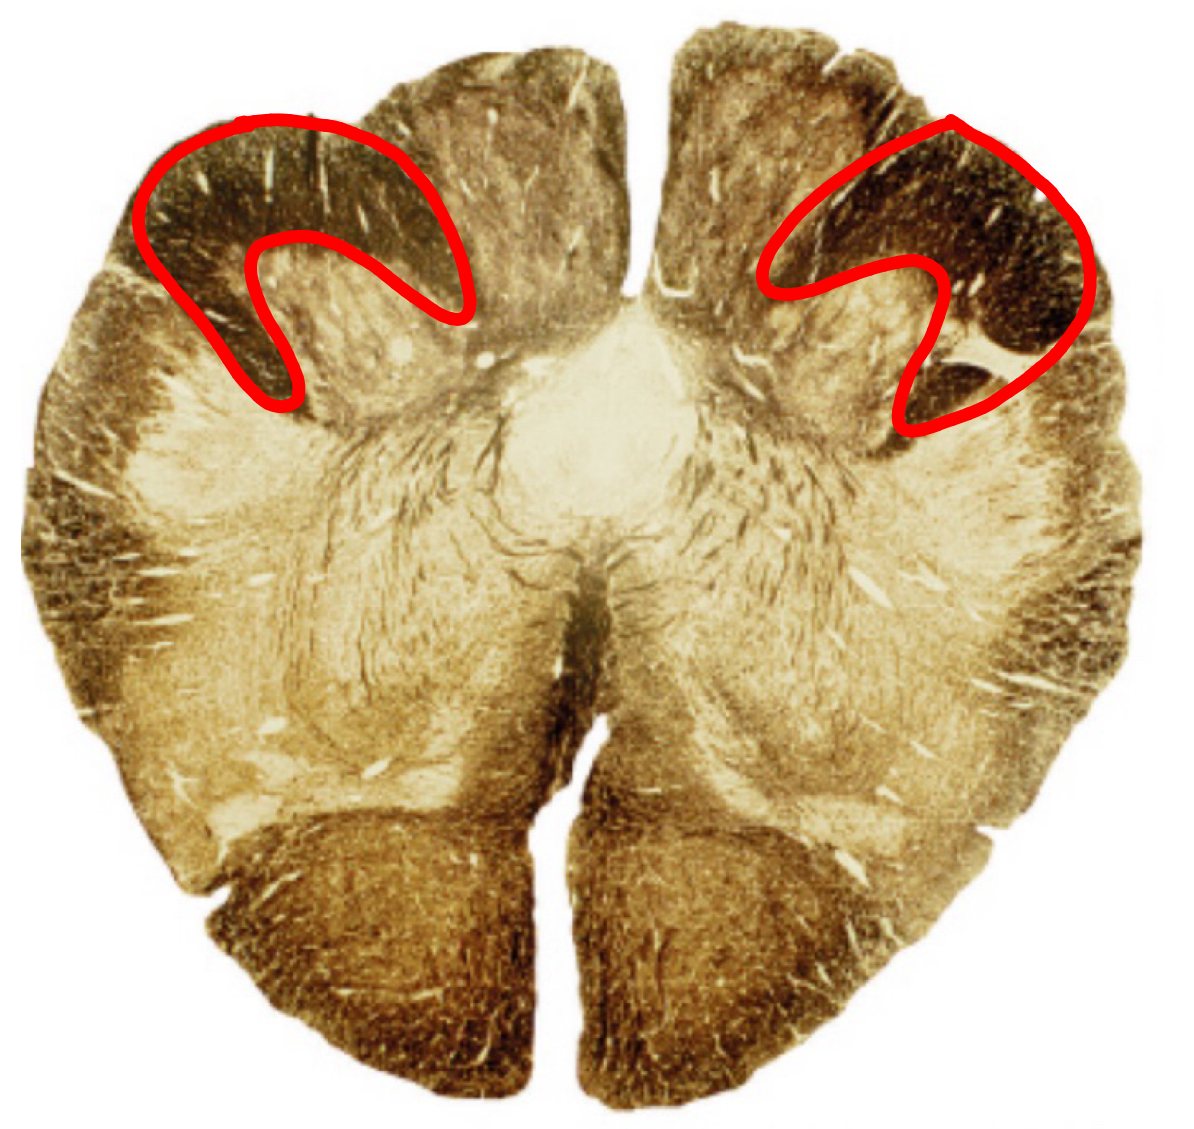

corticospinal + corticobulbar tracts rostral pons